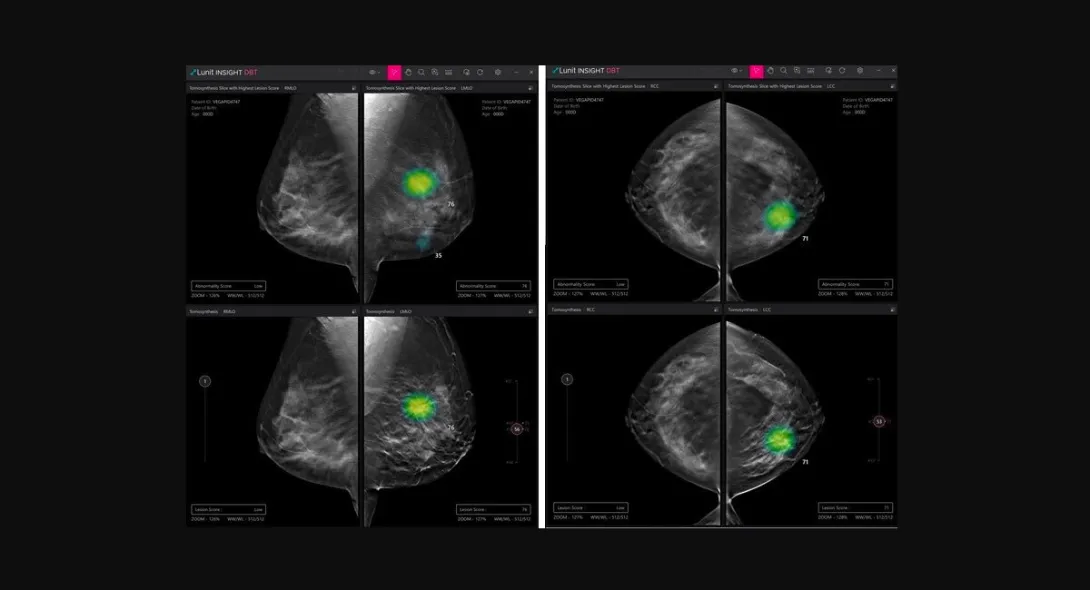

Lunit obtains new CE mark for AI DBT solution

South Korean medical AI company Lunit has received a CE mark under Europe's latest Medical Device Regulation for its AI software for digital breast tomosynthesis (DBT) analysis.

Called Lunit INSIGHT DBT, the software solution analyses 3D images from DBT, enabling fast and accurate diagnosis of breast cancer.

In a press statement, Lunit disclosed its plan to start rolling out the software product in Europe by the end of March, noting an uptick in interest. It also announced its plan to begin the process of acquiring the US FDA's approval for Lunit INSIGHT DBT in the third quarter. The technology has already been approved for commercialisation in South Korea early this year.